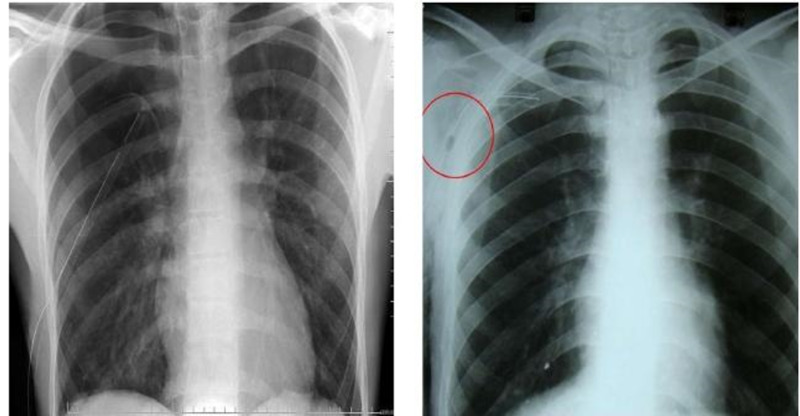

- Chụp X-quang ngực: Giúp phát hiện dịch hoặc các bất thường khác trong ngực.